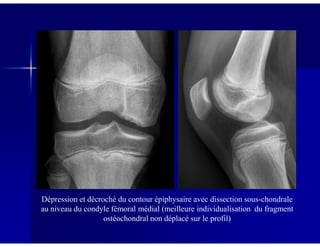

Dépression et décroché du contour épiphysaire avec dissection sous-chondrale

au niveau du condyle fémoral médial (meilleure individualisation du fragment

ostéochondral non déplacé sur le profil)

Image claire sous-chondrale au niveau du condyle fémoral

médial avec densification du spongieux adjacent